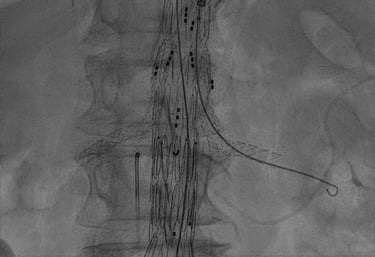

ENDOPROTESI AORTICA PERCUTANEA

Endoprotesi aortica percutanea: si tratta del trattamento percutaneo, attraverso le arterie femorali, degli aneurismi (dilatazioni) dell'aorta, nel suo decorso nell'addome. E' una metodica utilizzata in pazienti non idonei alla chirurgia.